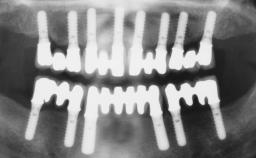

Immediate Loading of Six Implants in the Mandible and Six Implants in the Maxilla and Final Restoration with Full-Arch CAD/CAM Metal Framework FDPs Involving Digital Planning and Guided Surgery

Immediate loading of dental implants is increasingly popular with clinicians and patients. The idea of delivering a restoration directly after implant insertion,combined with a less invasive procedure (flapless protocol), has made treatment protocols involving dental implants more accessible to dentists and patients. However,immediate-loading concepts require sophisticated and exact planning. To facilitate this, conventional panoramic tomographs and periapical radiographs are often taken with the patient wearing a radiographic template simulating the preoperative prosthetic design. However, these radiographs do not provide all the necessary information. In addition, some protocols call for conventional surgical templates fabricated on the diagnostic cast. These will inform the bone drilling points and drill angles, but do not reference the underlying anatomical structures or provide exact 3-D guidance.

# of Implants 12

Guided Surgery Yes

Defining Characteristics Fully edentulous upper jaw to be rehabilitated with four or more implants

Modality 6+ implants with immediate loading